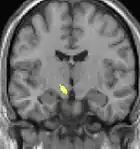

Positron emission tomography (PET) scans indicate the brain areas which are activated during attack only, compared to pain free periods. These pictures show brain areas that are active during pain in yellow/orange color (called "pain matrix"). The area in the center (in all three views) is specifically activated during CH only. The bottom row voxel-based morphometry (VBM) shows structural brain differences between individuals with and without CH; only a portion of the hypothalamus is different.[33]